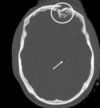

Which of the following mechanism of TBI is depicted in the CT?

1- Skull fracture

2- Contusion (bruise)

3- hematomas (blood clots)

4- lacerations (tear)

5- Diffuse axonal injury (nerve damage)

A